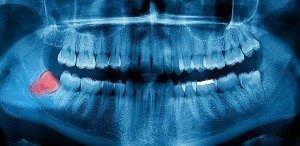

The earliest that we usually begin to screen for wisdom tooth anomalies is between the ages of 14 or 15. At this time, we use a panoramic x-ray taken to assess the development of the bite – as well as the location of the wisdom teeth.